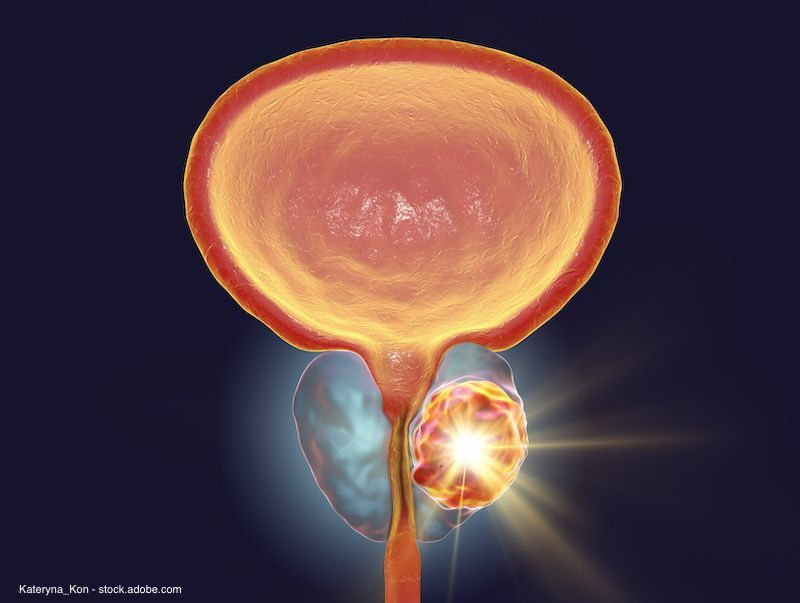

Impact of raising testosterone levels in men after radical prostatectomy

Investigators found that about one-fourth of men who underwent the “testosterone challenge” had a rise in PSA level.

A “testosterone challenge” approach appears to allow for early detection of prostate cancer recurrence in men with low testosterone after radical prostatectomy (RP), according to a study presented at the 2021 Sexual Medicine Society of North America Fall Scientific Meeting.1

The investigators found that 5 of 22 men who underwent the challenge had a rise in prostate-specific antigen (PSA) level following testosterone therapy.

Given that PSA secretion is testosterone-dependent, the investigators sought to raise testosterone levels in men who had undergone RP and analyze the effects. This would determine whether low testosterone levels in this group of men were factors in producing artificial, undetectable PSA levels.

Twenty-two patients were evaluated, including men who underwent RP with an undetectable PSA level and a total testosterone level of less than 200 ng/dL. Mean preoperative PSA among this population was 6.2 ng/mL, mean post-RP total testosterone value was 140 ± 35 ng/dL 2.2, median Gleason sum (GS) was 7 (23% had a GS of greater than or equal to 8), mean post-RP pre-challenge testosterone value was 140 ± 35 ng/dL, and mean time from RP to testosterone challenge initiation was 7 ± 9 months.

Over the course of this study, patients underwent an in-office intramuscular injection of 100 mg of testosterone cypionate and were then checked for PSA level after 5 days. PSA level had to be undetectable every month following the testosterone challenge in order for patients to get another injection at 3 months and every 6 months after that. Follow-up occurred at least 24 months after initiating testosterone therapy. The mean TT value 5 days after starting the testosterone challenge was 640 ± 220 ng/dL, and all patients at this point had TT levels above 400 ng/dL.

The investigators found that 5 out of 22 men experienced an elevated PSA level after the testosterone injection, 2 of whom experienced immediate rises in PSA.

All other men in this study started testosterone therapy immediately and experienced PSA elevation at 9, 14, and 22 months after initial injection (PSA values 0.08 ng/mL, 0.12 ng/mL, and 0.11 ng/mL). Patients who had PSA elevation demonstrated a continual rise in PSA level and had detectable disease on imaging. Those who had PSA recurrence had either GS 7 with unfavorable pathology (2/22) or GS of at least 8 (3/22).

“This T challenge approach permits the early detection of prostate cancer recurrence permitting early intervention. About 10% of such men had a PSA rise immediately after T challenge,” concluded first author Jose Miguel Flores Martinez, MD, Memorial Sloan Kettering Cancer Center, and his coinvestigators.